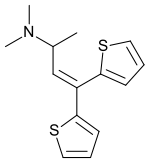

The pharmacodynamic response to an opioid depends upon the receptor to which it binds, its affinity for that receptor, and whether the opioid is an agonist or an antagonist. For example, the supraspinal analgesic properties of the opioid agonist morphine are mediated by activation of the μ1 receptor; respiratory depression and physical dependence by the μ2 receptor; and sedation and spinal analgesia by the κ receptor. Each group of opioid receptors elicits a distinct set of neurological responses, with the receptor subtypes (such as μ1 and μ2 for example) providing even more [measurably] specific responses. Unique to each opioid is its distinct binding affinity to the various classes of opioid receptors (e.g. the μ, κ, and δ opioid receptors are activated at different magnitudes according to the specific receptor binding affinities of the opioid). For example, the opiate alkaloid morphine exhibits high-affinity binding to the μ-opioid receptor, while ketazocine exhibits high affinity to ĸ receptors. It is this combinatorial mechanism that allows for such a wide class of opioids and molecular designs to exist, each with its own unique effect profile. Their individual molecular structure is also responsible for their different duration of action, whereby metabolic breakdown (such as N-dealkylation) is responsible for opioid metabolism.

There are a number of broad classes of opioids:[260]

- Fully synthetic opioids: such as fentanyl, pethidine, levorphanol, methadone, tramadol, tapentadol, and dextropropoxyphene;